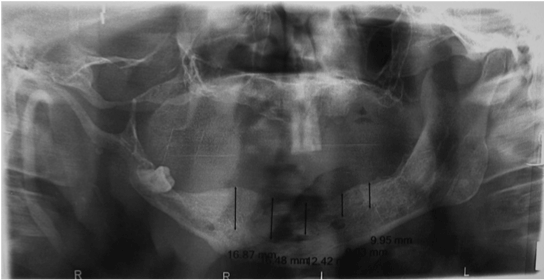

| Figure 4: Preoperative panoramic radiograph of the patient with 2D data planning for implantation; Characteristic finding- increase in bone density, enlarged mandibular foramen, lateral bowing of the mandibular ramus, increase in dimensions of the coronoid notch, and a decrease in the mandibular angle. |